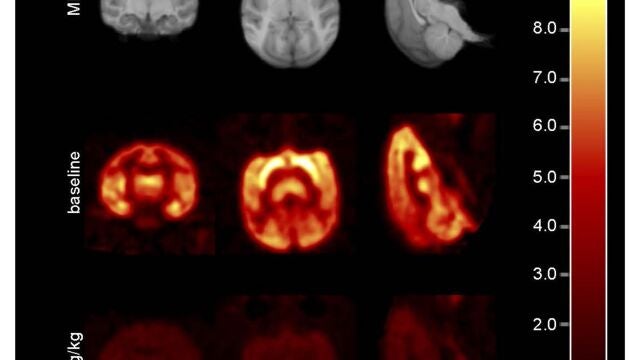

Imágenes de resonancia magnética y de una tomografía de un mono antes y después de recibir el BMS-984923 | EFE/J. Spurrier Science Translational Medicine

Los investigadores han comprobado por primera vez, gracias a las imágenes de resonancias magnéticas y tomografías, cómo el fármaco actuaba con eficacia sobre los receptores mGluR5 del cerebro de los monos y ratones, sin causar efectos secundarios.